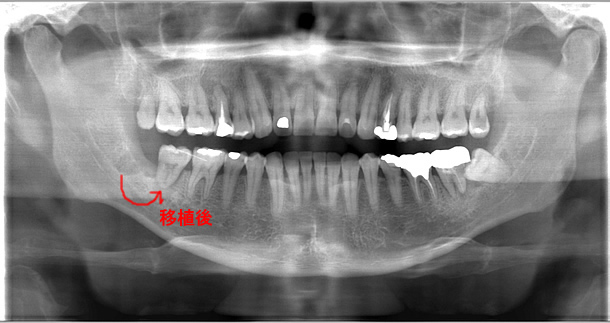

右下第一大臼歯は根の1/4付近まで虫歯に侵され、その影響で根分岐部病変も併発しており保存不可能な状態。

通常は抜歯してインプラントにするかあるいは前後の歯を削ってブリッジにするしかないが、右上奥に使われていない親知らずが存在し、移植の説明をおこなった。

患者様の同意が得られたため、自家歯牙移植を試みることになった。